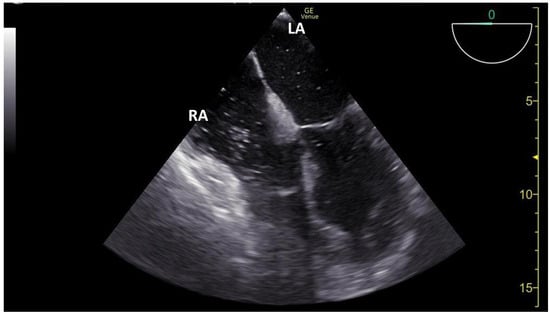

3.1. TCCD MES-Positive Case 1

3.2. TCCD MES-Positive Case 2

3.3. TCCD MES-Positive Case 3